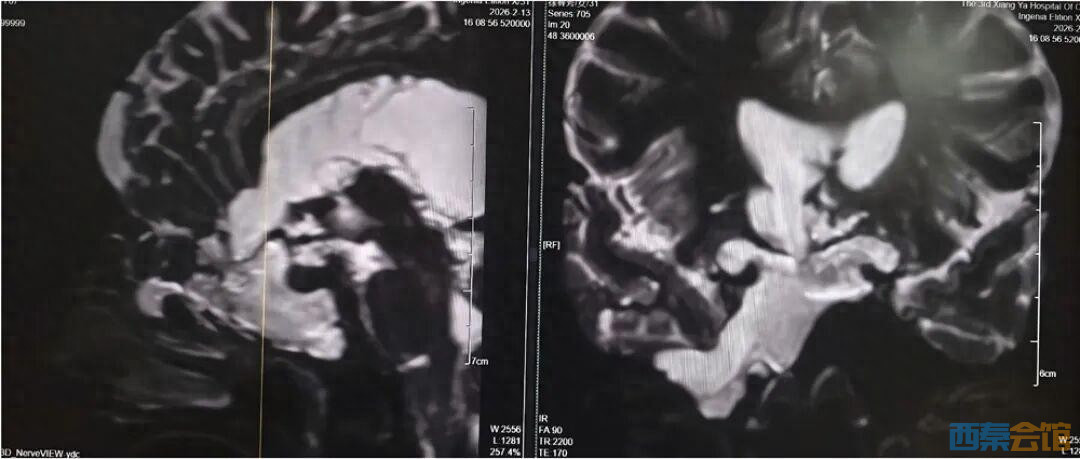

女子“脑子漏水”长达4年,最终神志模糊险丧命!专家:流清水鼻..